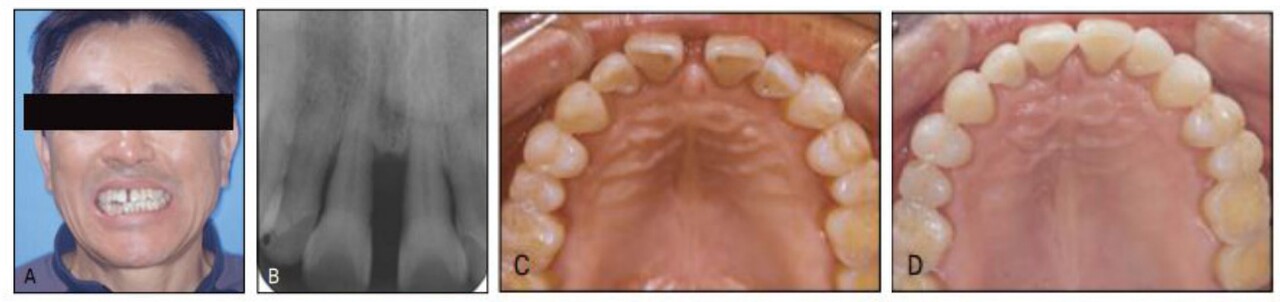

한편, 고령자일수록 이전의 치주질환으로 인해 병적치아이동 (pathologic tooth migration) 이 나타난 빈도나 정도가 심하다는 것이다. 상악 전치부의 경우 염증으로 인해 돌출과 함께 치간공간이 나타나는데 객관적으로도 비심미적이고 환자들 또한 이를 매우 싫어한다. 같은 치간 공간이라도 전체적인 치아크기가 작아서 나타난 경 우와 달리, 병적치아이동은 치주염이 심한 부위의 치아가 두드러지게 이동되어 매우 비심미적이며 나이 고하를 막론하고 모든 환자들이 이를 방치하고 그냥 두고 싶어하지를 않는다는 것을 볼 수 있다. 많이 이동된 치아를 발거하고 보철을 한다면 해당 치아뿐 아니라 인접 치아도 다수 발거해야 한다는 이야기에 주저하고, 컴포짓 치료는 치주질환을 더 악화시킨다하여 못하고 있다. 결국 자연치를 보존하면서 전치부 심미를 회복하는 유일한 방법이 교정치료인 바, 고령자의 교정치료 필요성이 최근 들어 크게 부각 되고 있다(그림 23-1).